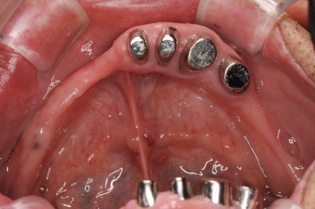

この方は結局、all on 4 を応用し、奥歯に両側2本のインプラントを傾斜埋入して、それにマグネットをつけました。これなら骨移植をせずにインプラントが可能になり、3ヶ月ほどで終了できます。

術後レントゲンです。このように斜めにインプラントをいれることにより、上顎洞への骨移植をさけることができます。これはオールオンフォーのインプラントを行っている歯科医ならではの発想です。